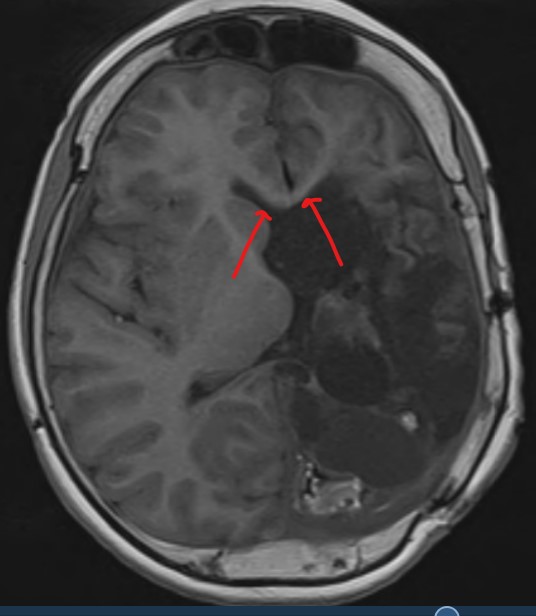

This is a more striking example:

While there is an asymmetry of beta frequencies on the common average montage, especially over the central-parietal regions, the asymmetry is easily missed. The bipolar montage demonstrates suppression of normal rhythms over the left hemisphere; the suppression over the left hemisphere cannot be appreciated on the referential montage. The EEG has been performed on a patient who has previously had a left hemispherectomy.